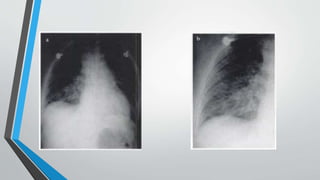

La insuficiencia cardiaca se define como la incapacidad del corazón para bombear sangre a una velocidad y cantidad adecuadas. Las causas afectan primero al ventrículo izquierdo y luego al derecho, resultando en insuficiencia ventricular. La radiología puede detectar signos de cardiomegalia, edema pulmonar, derrame pleural y patrón de "alas de mariposa". El índice cardiotorácico mide el grado de cardiomegalia y es útil para el diagnóstico de insuficiencia cardiaca.